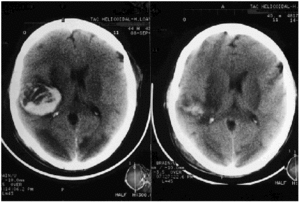

Al segundo día de hospitalización en la UCI aparecieron signos de focalización (anisocoria y hemiparesia izquierdas), por lo que se solicitó una tomografía axial computarizada (TAC) cerebral, hallándose hemorragia intraparenquimal corticosubcortical temporoparietal derecha con colapso ventricular y desplazamiento de la línea media, así como áreas isquémicas en los lóbulos occipitales y en los núcleos lenticulares (fig. 1).

Figura 1. Imagen pre y posquirúrgica de hemorragia intraparenquimal corticosubcortical temporoparietal derecha que causa colapso ventricular y desplazamiento de línea media. Se asocian áreas isquémicas en los lóbulos occipitales y en los núcleos lenticulares.

Por estos motivos, el paciente fue urgentemente intervenido, realizándose una craniectomía y la evacuación de hematoma intraparenquimatoso derecho (fig. 1).